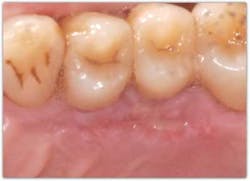

There is certainly no panacea for treatment, but we have found this combination therapy provides our patients with long-term predictable, stable results. Our preferred treatment method for gingival recession defects affecting one to four teeth is to use a tunneling technique in combination with a subepithelial connective tissue graft, enamel matrix derivative, and a coronally advanced flap (figures 4-9). When treating four or more teeth, or if a patient is opposed to harvesting a SCTG, we use a tunneling procedure in conjunction with an acellular dermal matrix graft, enamel matrix derivative, and a coronally advanced flap.